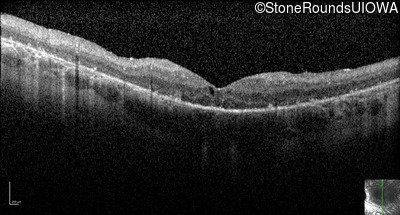

Optical Coherence Tomography - Right - 20/40

Exemplar / OCT Stack